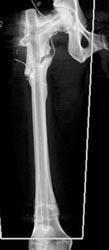

Non Union of Tibial Fracture